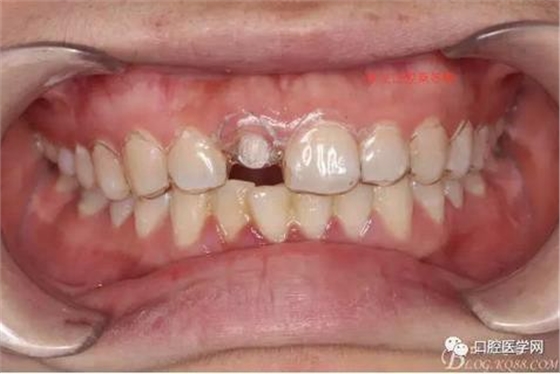

術(shù)前口內(nèi)照,11殘根,唇側(cè)牙齦紅腫,肩臺在齦下2毫米,舌側(cè)正常.21有被動萌出,長寬比例不協(xié)調(diào)??谇恍l(wèi)生一般,有菌斑。

術(shù)前原有牙冠復(fù)位,牙齦紅腫。